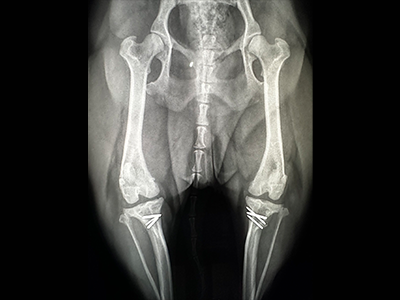

当院では、骨折・脱臼・椎間板ヘルニア・リウマチ性関節炎などの整形外科疾患に対して、専門医による幅広い診療を行っています。

動物も同じです。当院では、より的確な診断と最善の治療のために、骨と関節のスペシャリストに診てもらう体制を整えています。

手術が必要な症例はもちろん、慢性的な痛みや関節の違和感など、内科的な管理が必要なケースについても対応できるよう、DVMsどうぶつ医療センター横浜 整形外科医長・伊澤 幸甫先生を定期的(毎週月曜日)にお招きし、診断・治療を行っています。

当院の健康診断では、血液・尿・超音波などの基本的な検査に加えて、関節のレントゲン撮影も実施しています。

これは、「将来の痛みや歩行の問題を早期に発見したい」という想いからです。

「健康診断=内臓のチェック」だけにとどまらず、骨や関節、歯までを含めたトータルケアを実現しています。